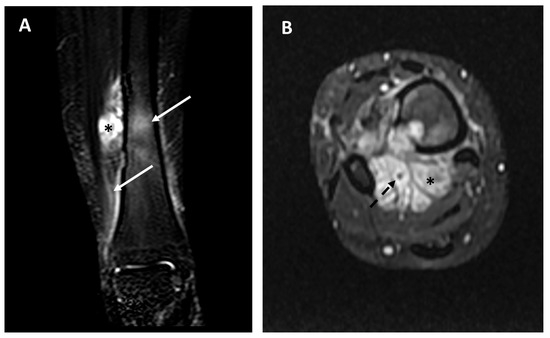

Imaging Analysis for Metastatic Risk Assessment in Adamantinoma: The Aid of Radiology in the Absence of a Histological Grading—An MRI-Based Risk Model Proposal

Background: Adamantinoma is a very rare primary malignant bone tumor. A histopathological grading is still lacking, and as a result, metastatic risk stratification at diagnosis is challenging. Due to this, imaging could play a role in prognosis prediction and treatment strategy assessment. We aimed to evaluate baseline imaging features and their correlation with the development of metastatic disease. Methods: We retrospectively collected clinical (metastatic disease) and radiological data at baseline (Conventional Radiography, CT, MRI) of all consecutive patients with a histopathological diagnosis of adamantinoma at our sarcoma center between 2006 and 2022. Tumor location, dimensions, main radiological pattern (lytic, sclerotic, mixed), Lodwick–Madewell grading, periosteal reaction, multifocality, soft-tissue extraskeletal component, peritumoral edema, peritumoral enhancement, and vascular invasion were analyzed. Associations between the above-mentioned radiological features and metastatic disease at diagnosis or during follow-up were assessed. Results: Twenty-two patients were included (15 [68.2%] women, median age 27 years old, range 7–58 years old). Six out of twenty-two patients (27.3%) developed distant metastases (only two of them were dedifferentiated adamantinoma): two patients (9%) presented with metastatic disease at diagnosis, while four patients developed metastases during follow-up (18.2%). The following radiological features represent a significant risk for metastatic disease (p = 0.01): (i) presence of an extra-skeletal component (Odds Ratio [OR] = 75.40; 95% CI = 3.15–1802.71), (ii) vascular invasion (OR = 121.00; 95% CI = 4.28–3424.73), (iii) diffuse peritumoral edema (OR = 75.40; 95% CI = 3.15–1802.71), (iv) peritumoral enhancement (OR = 84.33; 95% CI = 2.93–2423.26). All other features analyzed were not significantly associated with the onset of distant metastases. Based on these above-mentioned MRI features, we built two risk models for metastatic disease (excluding peritumoral enhancement, which was not available in five patients, to be applicable on unenhanced MRIs): Model (A) = simultaneous presence of two of those three features (2/3) with a sensitivity of 100% (54.07–100%) and a specificity of 93.75% (69.67–99.84%). Model (B) = simultaneous presence of all three features (3/3) with a sensitivity of 83.33% (35.88–99.58%) and a specificity of 100% (74.1–100%). Conclusions: An accurate evaluation of baseline imaging studies (particularly MRI) in patients affected by adamantinoma may significantly aid in prognosis prediction and the selection of high-metastatic-risk patients. For these patients, strict follow-up controls and more aggressive treatments should be suggested after multidisciplinary discussions in sarcoma centers. Full article

Show Figures

Figure 1